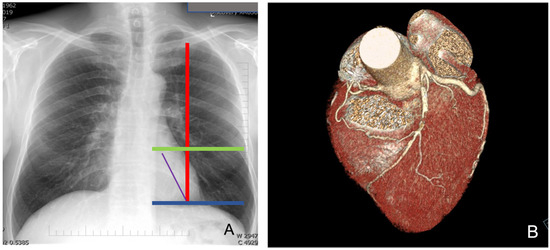

Computed tomography (CT) (third-generation 192-slice dual-source SOMATOM Force, Siemens Healthineers, Erlangen, Germany) and chest X-ray are commonly performed to delineate the heart anatomy and its relationships with the surrounding thoracic structures (Figure 1A,B).

More specifically, chest X-ray provides an initial indication of the left heart ventricle volume and the position of its free margin relative to the chest wall and intercostal space. As depicted in Figure 1A, we mark the mid-clavicular line and two horizontal lines that include the left second cardiac arch, corresponding to the left ventricle, allowing us to identify the possible position of the LAD with respect to these markers. This is very important to guide the positioning of ports, particularly the port for the endoscopic camera and for anchoring the left robotic arm; a bigger left ventricle requires a more medial port location to avoid competition between the instruments and beating heart. In addition, the LAD position can give indications on the effectively lateral site of the left mini-thoracotomy required for bypass grafting after mammary artery harvesting.

A CT scan or CT-ANGIO scan is useful in preoperative planning because it gives data on the size, position and quality of the left internal mammary artery and left anterior descending coronary artery (LAD). Indeed, the degree and site of any calcification of target vessels and any intramyocardial course of LAD can be assessed. A CT scan with 3D reconstruction can more accurately describe the relationship between the LAD and the chest wall, aiding in the selection of the intercostal space for thoracotomy.

Figure 1. Preoperative chest X-ray (A) and CT-scan with 3D reconstruction (B).